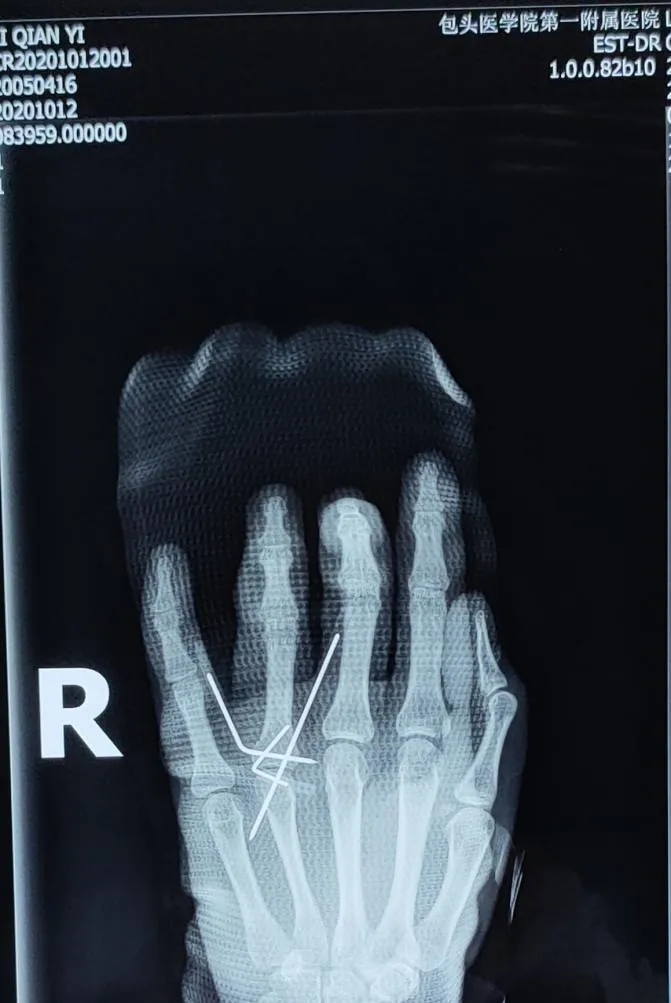

在完成相关检查后,小李被确诊为单指不全切断、开放性指骨骨折、手部指屈肌腱损伤等,手足踝外科医生连建强与同事们迅速为小李制定了手术计划,通过严谨细致的手术治疗,小李受伤的手部慢慢得到了恢复,骨折处复位良好,手指可轻微活动。目前,小李已在家属的陪伴下顺利出院,在家进行休养。